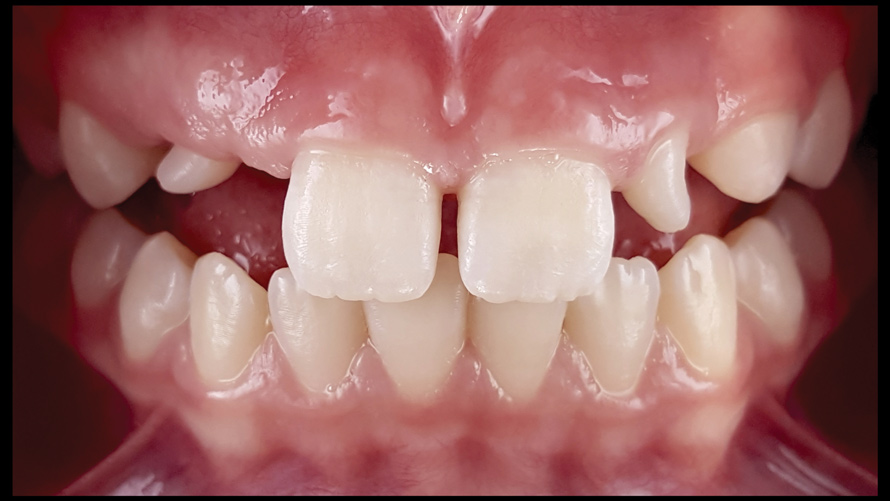

(9.) Preoperative esthetic case documentation using a smartphone and an EALS device.

Figure 9

(10.) Preoperative esthetic case documentation using a smartphone and an EALS device.

Figure 10

(11.) Preoperative esthetic case documentation using a smartphone and an EALS device.

Figure 11

(12.) Intraoral photographs taken with a smartphone and an EALS device for orthodontic evaluation.

Figure 12

(13.) Intraoral photographs taken with a smartphone and an EALS device for orthodontic evaluation.

Figure 13